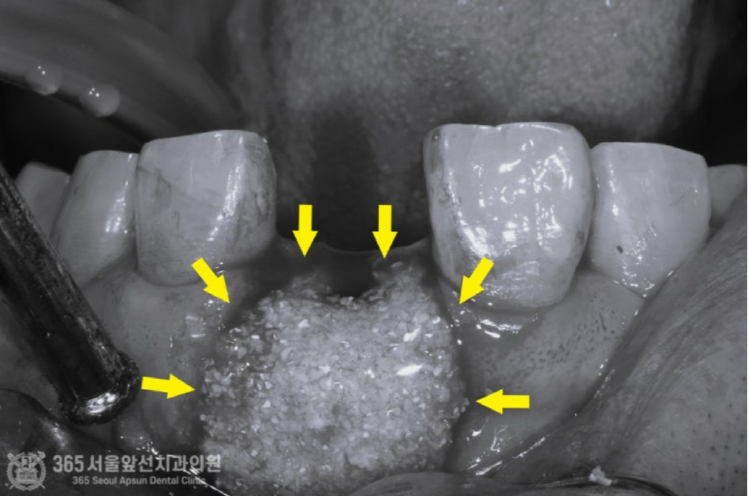

촬영일시 : 2024.07.02. 풍치로 인한 염증 부위를 색상으로 표시해보았습니다. (노란색) 3차원 CT를 이용하여 분석해보니 잇몸뼈가 염증으로 인해 녹은 상태로 매우 심각했습니다.....ㅠㅠ 촬영일시 : 2024.07.02. 결국 해당 치아는 발치를 하게 되었고, 임플란트 식립과 동시에 염증으로 인해 없어진 뼈를 재건하는 골이식을 시행하게 되었습니다. 발치를 하고 나서 임플란트 식립 및 골이식 수술 전 확인해보니 염증으로 소실된 뼈가 상당합니다. 촬영일시 : 2024.07.02. 임플란트를 식립했고 그 위로 두툼하게 골이식을 시행합니다. 일반적으로 골이식은 흡수되는 양이 상당합니다. 그래서 앞니 부위와 같이 미적으로 중요한 부위에서는 자연스러운 잇몸의 볼륨을 위해서 흡수되는 양을 감안하여 많은 양의 골이식을 시행하고있습니다. 임플란트를 식립 후에는 보통 작은 임시틀니를 드리고 그걸 사용하시는 경우가 많은데요. 지금처럼 골이식이 많이 들어간 경우에는 임시틀니를 사용할 경우 이식한 뼈가 제대로 성숙되지 못하는 경우가 많기에 다른 방식의 임시치아를 해드리고 있습니다. 위 환자분께서도 붙이는 형태의 임시치아를 해드렸고 잘사용하셨습니다. 촬영일시 : 2024.11.01. 4개월이 지나서 임플란트가 뼈와 잘 결합되었구요. 이식한 뼈도 단단해졌기에 슬슬 본 뜰 준비를 해봅니다. 동그랗게 회색 단추가 달려있는데요. 치유지대주라고 부르는 구조물로 이걸 이용하여 본을 뜨게 됩니다. 촬영일시 : 2024.11.05. 완성된 최종 보철물입니다. 사실 중간에 임플란트와 연결된 임시치아를 사용하여 잇몸 모양을 잡아주는 과정을 거쳤는데요. 아쉽게도 해당 과정에 대한 사진이 없군요 ㅠㅠ 이렇게 섬세하고 복잡한 과정을 거쳐서 임플란트 치료가 마무리 되었습니다 ㅎㅎ 이식된 뼈 부위도 통통하게 뼈가 잘되어있습니다 ㅎㅎ 만족스럽습니다. 촬영일시 : 2024.11.05. 치료가 마무리 된 후 엑스레이 사진입니다. 최종 보철물 장착 완료까지 자연스럽게 잘 마무리되어 기분이 좋네요. 직원분께서 가족의 치료를 믿고 맡겨주셨고, 그에 보답할 수 있어 기분 좋은 치료 증례였습니다. 앞으로도 더 유익한 치료 증례로 찾아뵙겠습니다. 도화역치과 365서울앞선치과의원이었습니다. 감사합니다. [ 치료기간: 2024년 7월2일 ~ 2024년 11월 5일 ] ※ 365서울앞선치과의원의 모든 포스팅은 각 진료과 의료진이 직접 작성합니다. 365서울앞선치과의원 블로그의 임상 케이스 게시물은 환자분께 의학적으로 정확하고 상세한 정보를 드리기 위해 각 진료과 의료진이 직접 작성하며, 모든 증례 사진은 본원 의료진이 직접 시술한 증례를 촬영한 것으로, 의료법 제23조, 제56조에 의거하며 환자분의 동의를 얻어 포스팅에 사용하였습니다. 또한 해당 케이스는 본 환자분의 치료 결과이며, 환자 상태에 따라 치료의 결과는 달라질 수 있습니다. |